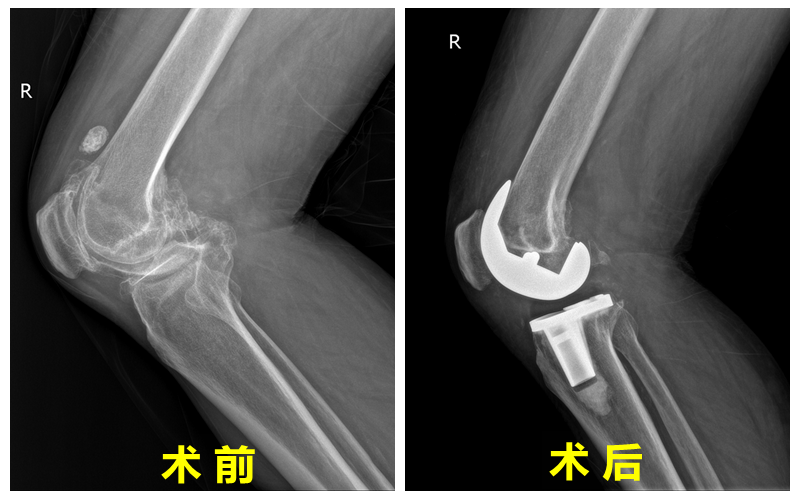

提到骨科手术,很多人第一印象往往是难以忍受的术后疼痛,以及较长的卧床时间。但78岁黄大爷在玉环市人民医院骨科顺利地完成了右膝关节置换手术治疗,术后一天予助行器辅助下地行走。

经过全面的检查和评估,陈文辉认为老人右膝骨性关节炎严重,建议实施人工关节置换术。术前详细规划,术中密切地团队协作,手术过程顺利,术后一天即可下床活动。由于对疼痛的精准管理和有效控制,老人丝毫感觉不到膝关节疼痛,完全可自行大小便,让患者和家人惊喜不已。

人工膝关节置换是目前膝关节严重骨性关节炎、关节畸形的最佳治疗手段,它可以迅速缓解疼痛,恢复关节功能,提高生活质量。近五年来,玉环市人民医院已有200多位患者接受人工膝关节置换手术,让许多患者生命更有质量。

膝关节置换手术的原理跟我们治牙是一样的:牙齿损坏以后,口腔医生会把坏掉的牙齿表面磨掉,再给坏牙带上一个“牙套”。同样,当我们关节表面的软骨彻底磨坏以后,就需要去掉磨坏的软骨面和部分软骨下骨,给关节换上一个新的金属“牙套”。